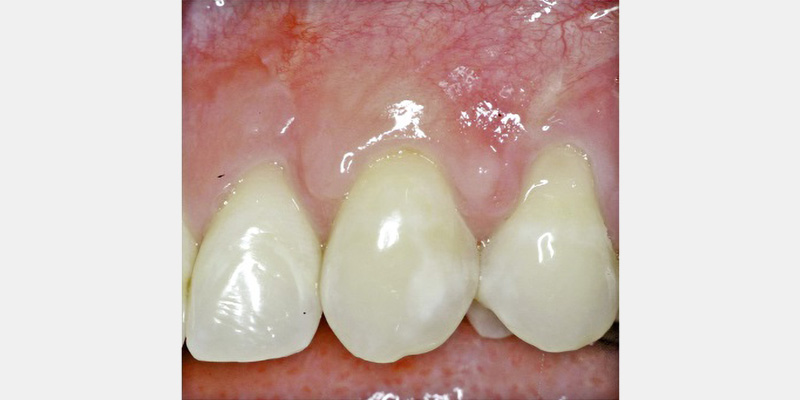

Effective augmentation techniques to treat more challenging esthetic concerns, such as open interproximal spaces and other severe oral soft-tissue deficiencies, are not currently available. Cell-based therapies may change this. Live cell-based therapy delivers multiple growth factors and can communicate more dynamically with host cells.

This facet of oral soft-tissue engineering involves the implantation of live cell-based skin substitutes or the in vitro construction of an autologous, transplantable vital tissue. Historically, one of the first bioengineered skin substitutes consisted of autologous expanded fibroblast grown from the patient’s own biopsies. One of the first dental studies using this autologous fibroblast transplantation evaluated the ability to expand interdental gingival soft tissue deficiencies.

Results showed the injection of autologous fibroblasts created significant improvement when compared to a placebo. Prior to the injection of these expanded fibroblasts, a “priming” procedure was performed in the papillary region to create an inflammatory response. The theory was to develop temporary increased tissue volume by causing inflammation, thus enabling the injection of more volume of the concentrated cell suspension. The cells were delivered 5-7 days after the priming procedure and then again at two other times following the first injection. The subjects were assessed at two, three and four months after the injections. Preliminary results indicate a novel tissue-engineering technique may hold promise in resolving the challenging open interproximal space.21 Further research is under way to evaluate this as a predictable therapy (Figs. 4A-4B).